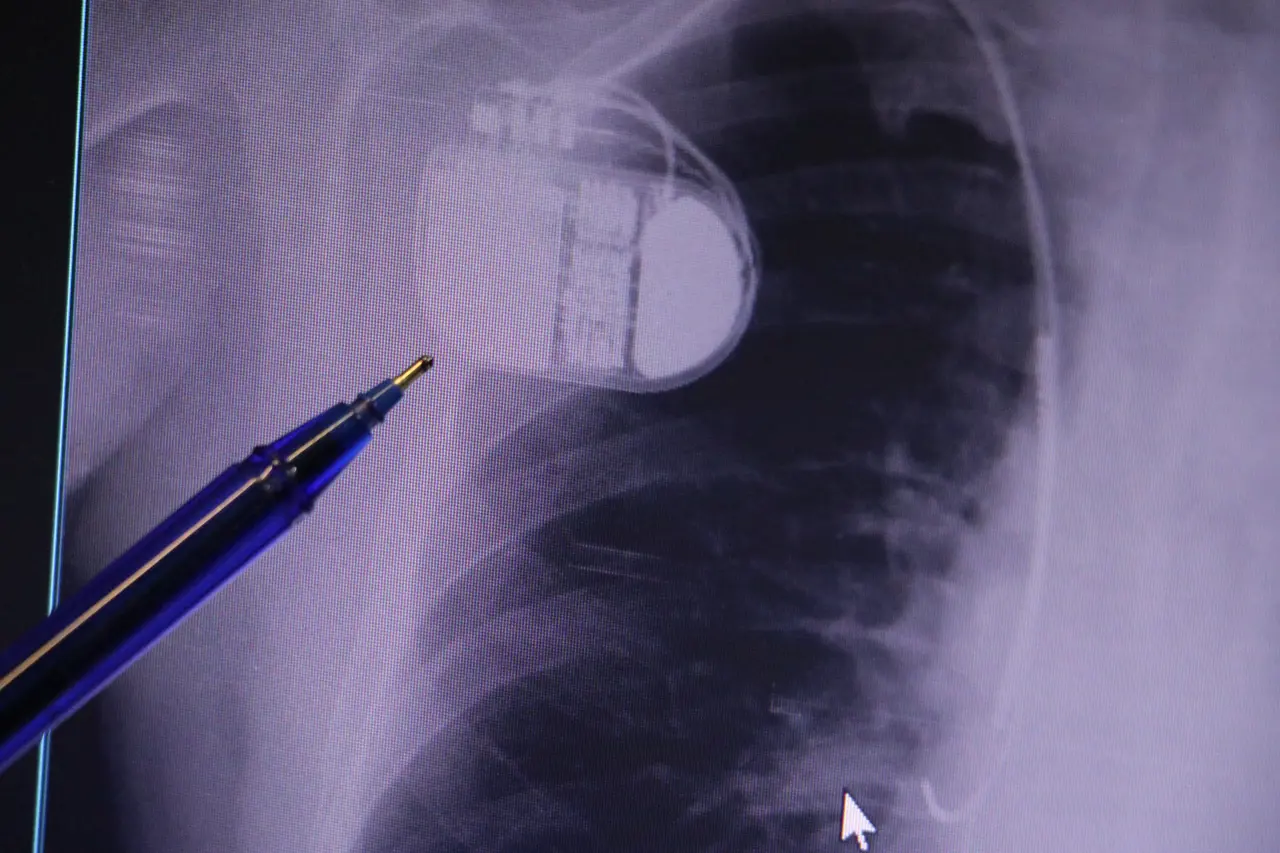

Konuya ilişkin açıklamalarda bulunan Sivas Medicana Hastanesi Kardiyoloji Bölümü Uzmanı Dr. İsmail Erdoğu, kalp pilinin önemine vurgu yaptı. Erdoğu, Yeni nesil kalp pillerinin MR cihazlarına girmeye imkan sağladığı, ancak tarama cihazlarından geçmenin önerilmediğini ifade ederek,

"Soğuk hava nedeniyle oluşan titremeler, kalp pilinin kalbin durduğunu sanmasına ve yanlış şoklamaya yol açabilir. Bu nedenle hastalarımızın bu dönemlerde daha dikkatli olmalarını öneriyoruz"

dedi.

Kalp pilleri ile MR cihazına girilebileceğini belirten Erdoğu,

"Çok büyük bir ameliyat değil ama yine de ciddi bir cerrahi işlem. Kalp pili, tıpta son 30 yılda yaşanan gelişmelerden en büyüğü. Bir bilgisayarın küçültülüp insan vücuduna konulmuş hali aslında. İnsan ömrünü ciddi oranda uzatan bir tedavi. İnsanlar bir şokla hayata tutunurken, pil olmasaydı öleceğini düşündüğümüz birçok hastamız var. Kalp pilinin bu özelliği, uygun hastalarda ciddi oranda ani ölümü engelliyor. Hastanın başına gelecek bir kalp durması durumunda yanında bir sağlıkçı yoksa, onun ritmini düzeltecek defibrilatör cihazı yoksa hastayı hayatta tutmak mümkün değil. Uygun endikasyonlarda kalp pili olduğu zaman, pil hastaların ritmini algılıyor ve acilde yapılan şoklamayı yaparak hastayı hayata döndürüyor. Kalp pillerinde yeni teknolojilerle MR'a girmek mümkün, tomografiye zaten girebiliyorlar. Tarama cihazlarından geçmelerini uygun görmüyoruz. Bu tarz durumlarda hastalarımız 'kalp pilim var' dediğinde muaf tutuluyorlar. Kalp pilleri ciddi teknolojik cihazlardır. Vücudun içindeki titreşimi, örneğin mikser kullanmak, kolunu sallayacak herhangi bir eylem kalp pilinde olumsuz etki oluşturabilir. Soğuk havalarda vücutta oluşan ciddi titremeler kalp pilinin hafızasını karıştırıp kalbin durduğunu düşündürebilir ve gereksiz şoklama yapabilir. Bu tarz kişilerin soğuk havalarda daha temkinli olması gerekir"

diye konuştu.